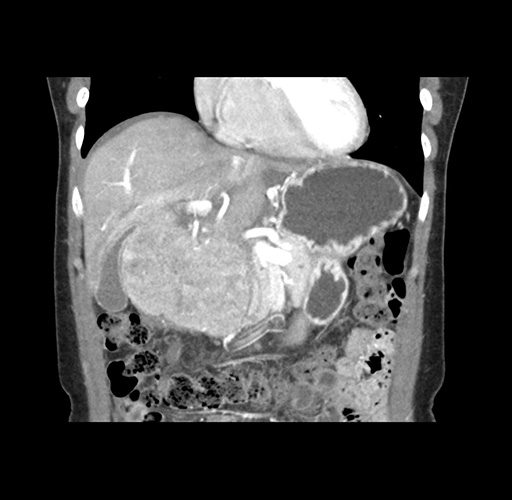

Imaging Analysis

Look through the patient's CT scan to identify any areas of concern for the necessary procedure.

Based on your CT findings, which issue(s) would give reason for "planned slowing down moment(s)" in this case?

Considering a standard left lateral sectionectomy procedure, what step(s) of the operation would you do differently in this case ?